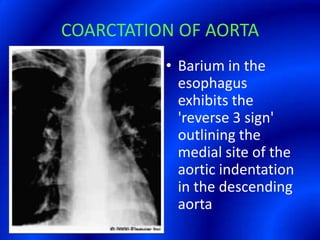

This document provides information about a barium swallow procedure. It begins with an introduction and overview of the embryology and anatomy of the pharynx and esophagus. It then describes the procedure itself, including preparation, technique, views obtained, and indications. Specific conditions that may be examined include pharyngeal and esophageal webs, foreign body impaction, scleroderma, dysphagia, mediastinal masses, and carcinoma. Diagrams are provided to illustrate normal anatomy and various pathological findings.